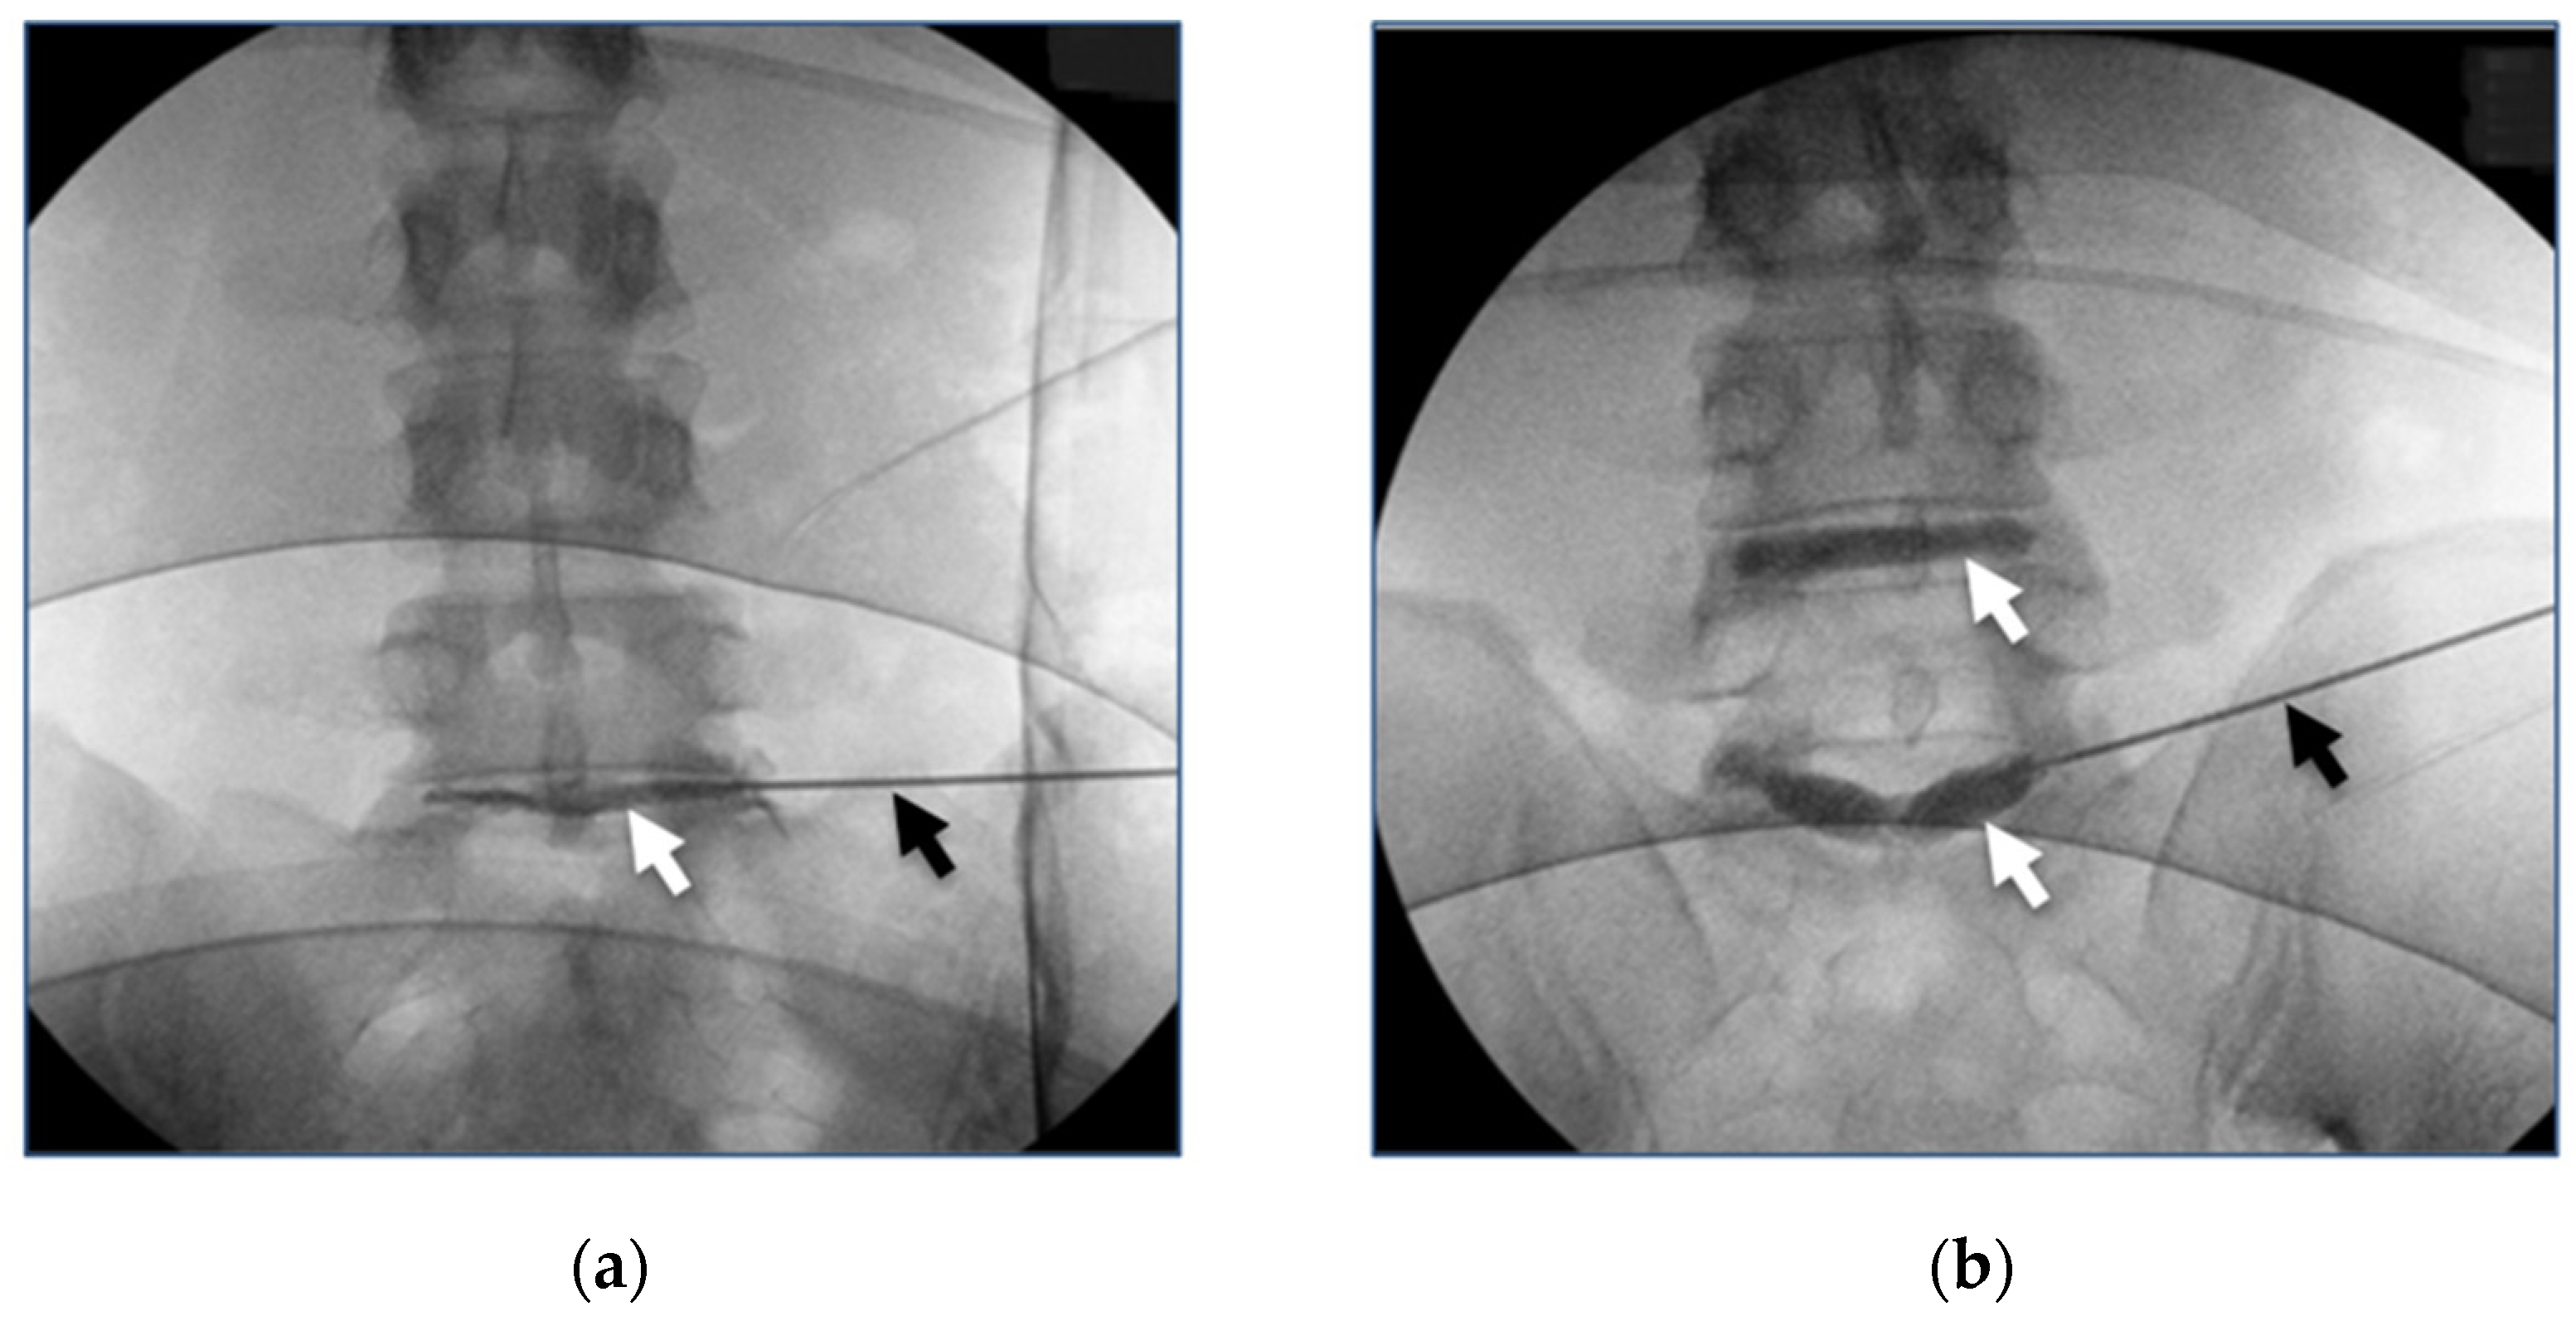

3.4. Clinical Studies Review